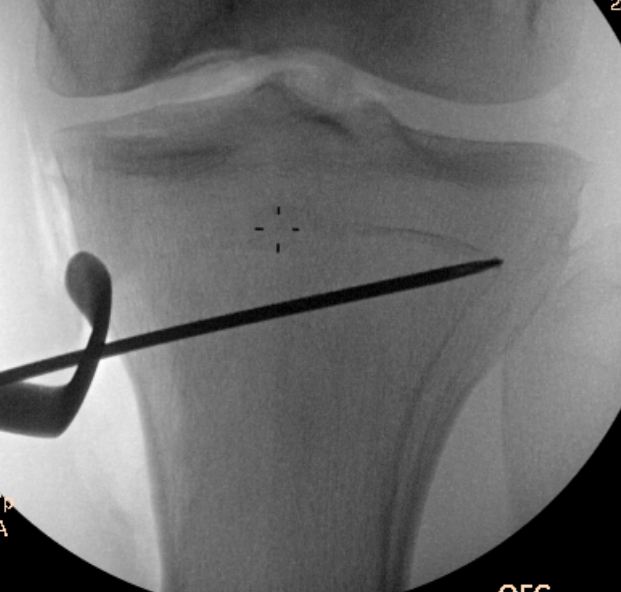

Guide pins for osteotomy and checking posterior slope

Osteotomy to within 1cm of the lateral cortex

Consider lateral hinge 2 mm K wire

- 10 mm from lateral cortex

- distal to proximal